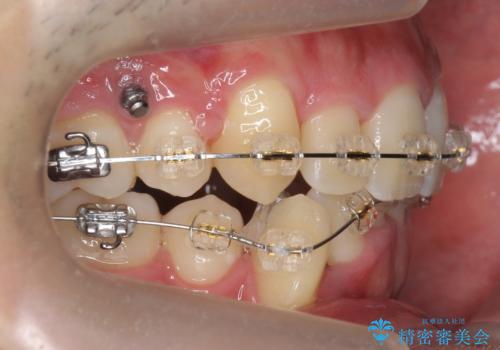

- ワイヤー矯正

上下左右の小臼歯を抜歯しています。

下のがたつきが大きいため、抜いたスペースをしっかり利用して並べるため矯正用インプラントを使用しています。